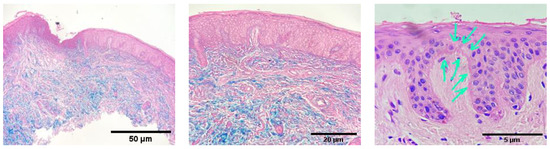

2. Clinical Experience—Case Report